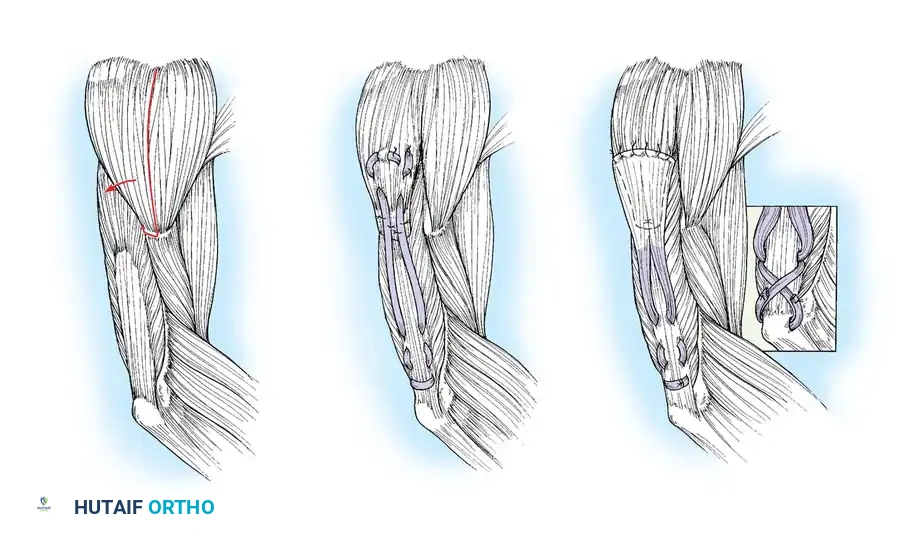

The posterior deltoid-to-triceps transfer, originally described by Moberg, is the gold standard procedure for establishing elbow extension. The posterior deltoid is synergistic with elbow extension and provides excellent excursion and power. Because the deltoid lacks sufficient length to reach the olecranon directly, the procedure requires an intercalated graft (fascia lata, toe extensors, or tibialis anterior tendon).

Lacey et al. reported excellent results using anterior tibial tendon grafts, noting that all patients achieved functional elbow extension and high satisfaction rates. Hentz et al. modified the procedure by utilizing fascia lata or directly attaching the deltoid to the mobilized triceps aponeurosis without a free graft, though this requires extensive mobilization.

Operative Technique: Posterior Deltoid-to-Triceps Transfer (Modified Moberg)

1. Make a 10- to 13-cm longitudinal incision along the posterior border of the deltoid muscle, extending distally toward the humeral insertion.

2. Raise thick fasciocutaneous flaps over the fascia of the deltoid to prevent skin necrosis. Identify the deltoid's humeral insertion.

3. Using a periosteal elevator and sharp dissection, elevate the posterior third to half of the deltoid tendon along with a robust strip of its periosteal insertion.

Surgical Pitfall: When splitting the deltoid muscle fibers in a distal-to-proximal direction, you must carefully palpate and visually inspect the deep surface of the muscle. The axillary nerve and posterior circumflex humeral vessels enter the muscle on its deep surface. Injury to the axillary nerve will denervate the transfer, resulting in catastrophic failure.

Graft Harvesting and Preparation:

1. Depending on surgeon preference, harvest an appropriate intercalated graft. Moberg originally utilized great toe extensors; however, the anterior tibial tendon or a robust strip of fascia lata is currently preferred due to superior tensile strength.

2. If using fascia lata, harvest a strip approximately 4 cm wide and 15 cm long. Tubularize the graft using a running locking non-absorbable suture.

Tendon Weaving and Fixation:

1. Weave the proximal end of the graft into the mobilized posterior deltoid muscle belly using a Pulvertaft weave technique. Secure it with multiple interrupted horizontal mattress sutures (e.g., 2-0 Ethibond or FiberWire).

2. Expose the distal triceps tendon and olecranon via a separate posterior longitudinal incision.

3. Create a longitudinal split in the triceps aponeurosis.

4. Pass the distal end of the graft subcutaneously from the proximal incision to the distal incision. Ensure the subcutaneous tunnel is wide enough to allow unhindered gliding of the graft.